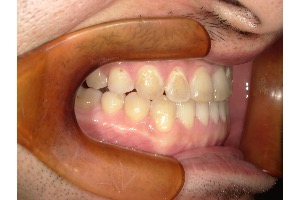

「受け口」とは、下の歯が上の歯よりも前に出ている噛み合わせのことを指し、専門的には「反対咬合」と呼ばれます。

受け口をそのままにしておくと、上下の歯の噛み合わせが自然な形からずれてしまい、食べ物をしっかり噛むことが難しくなります。その結果、以下のような問題が起こります

- 歯への偏った負担:噛む力が特定の歯に集中し、歯がすり減ったり、ひび割れたりする原因になります。